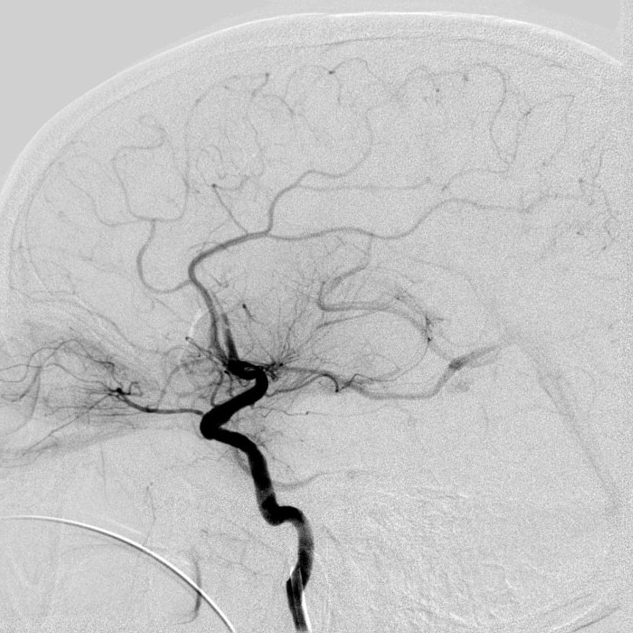

4*20mm Trevo ProVue取栓支架释放,5分钟后抽拉结合取栓,一次取栓,大脑中动脉完全再通。

大脑中动脉完全再通。